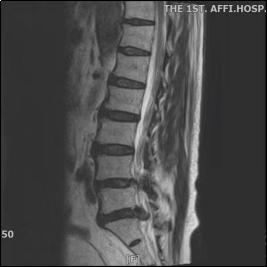

疼痛科主任舒雅接诊后,首先对王大叔进行查体等一系列检查,发现王大叔腰椎生理曲度变浅,腰部肌肉痉挛性紧张,腰3-4、腰4-5、腰5-骶1棘间及棘旁压痛(+),伴左下肢后外侧明显放射痛至足底部;左侧梨状肌压痛,伴左下肢明显放射痛,左小腿外侧及足背部、足底皮肤感觉减退,左侧直腿抬高试验10°,VAS 评分 8—9分,腰椎MRI显示突出物超出椎管矢状位中线的50%,属于巨大型腰椎间盘突出症。

结合腰椎MRI及患者症状,王大叔确诊为巨大型腰椎间盘突出症同时伴有腰椎椎管狭窄。